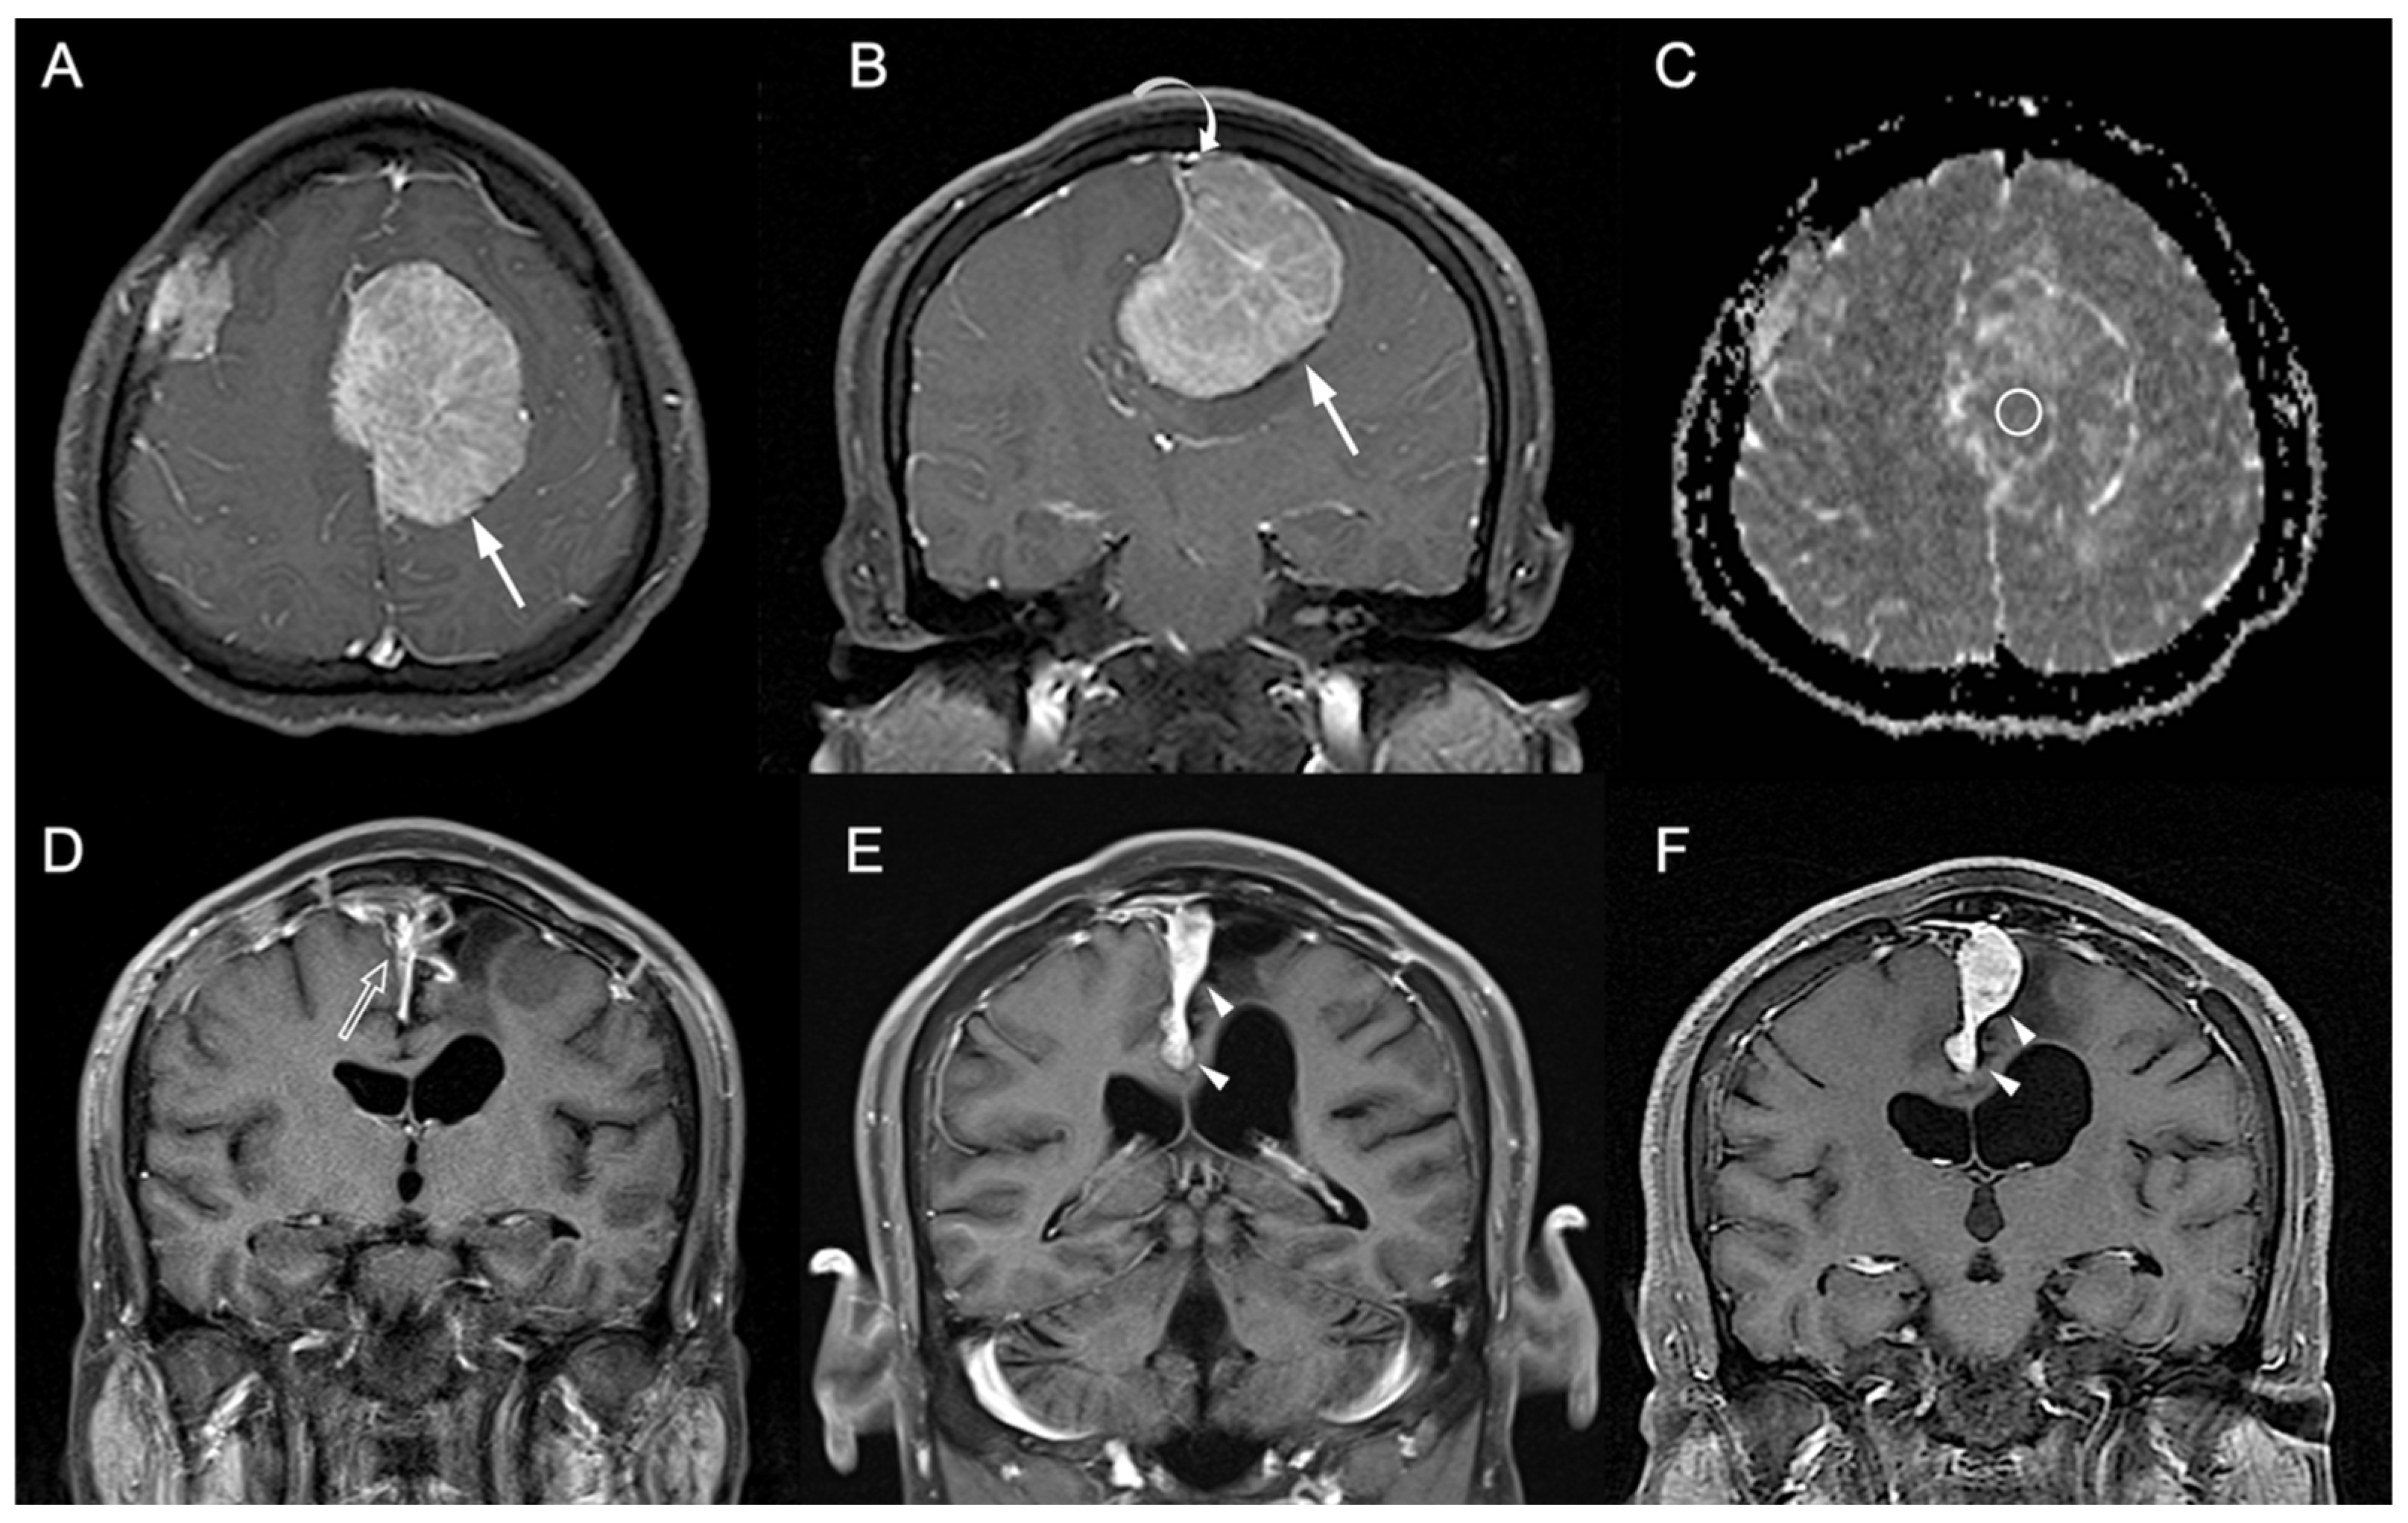

3.1. Clinical and Imaging Findings